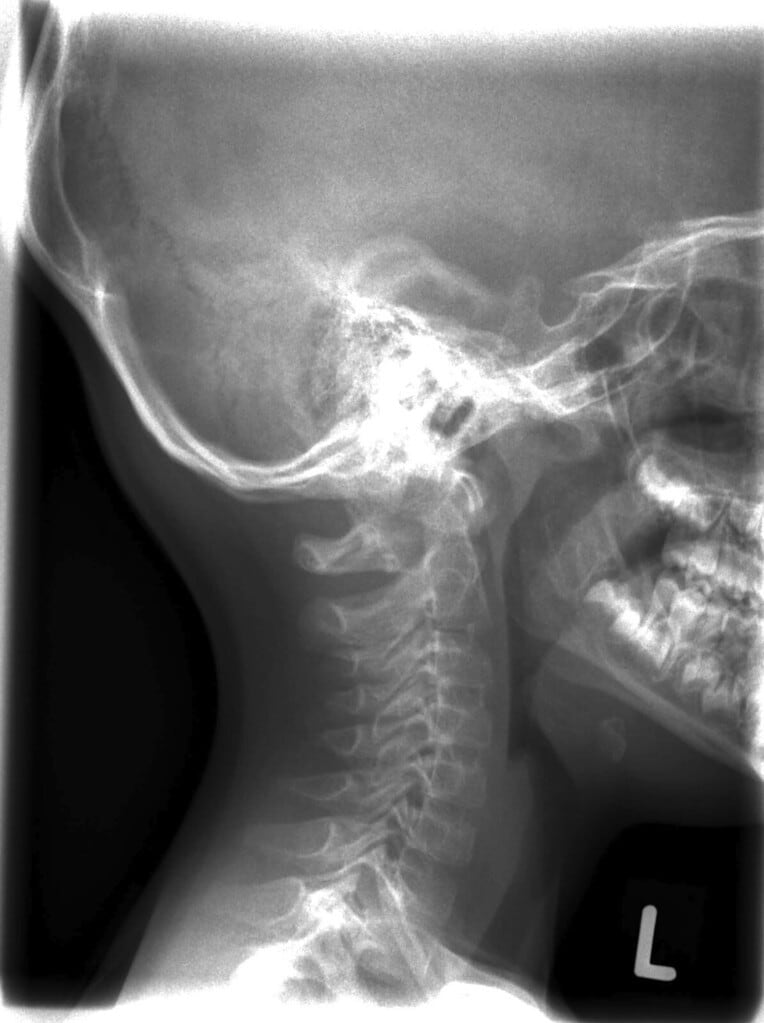

Zur weiteren Abklärung nutzen wir gezielt Röntgenuntersuchungen an Hals- und Lendenwirbelsäule. Häufig liegen Verspannungen im Nacken oder Kreuzschmerzen in Fehlfunktionen anderer Regionen, wie im Kau-/Kiefersystem, begründet. Außerdem untersuchen wir durch Tasten und Bewegen ihre Beweglichkeit, Spannungen und Blockaden.

In unserer Praxis erhalten Sie eine individuelle Behandlung, die auf Ihren Befunden und Beschwerden basiert. Nach einer gezielten Untersuchung und Auswertung von Tast- und gegebenenfalls Röntgenbefunden wird die Behandlung Ihrer Halswirbelsäule in Neutralhaltung durchgeführt. Mit gezielten Handgriffen werden Gelenke und Gewebe gelöst, Muskeln und Faszien behandelt und die Bewegungsfreiheit gefördert. Zusätzlich beraten wir Sie zu Haltung und Bewegung, um Beschwerden langfristig vorzubeugen und Ihre Gesundheit nachhaltig zu unterstützen.